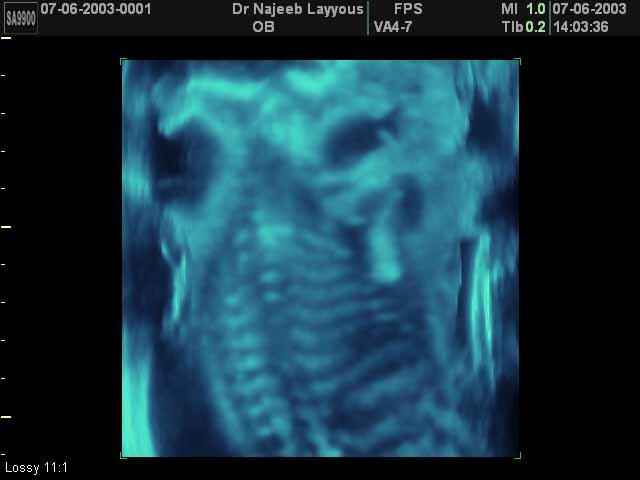

- Fetal Skeleton Ultrasound Photos

3D Ultrasound Scan Photos of Fetal Skeleton | Dr N Layyous